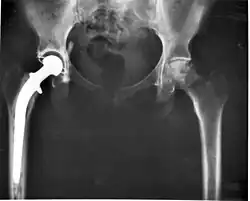

Geralmente é assintomática, apenas deixando os ossos mais vulneráveis a fraturas. Na radiografia caracteriza-se por imagens radilolucidas e na tomografia por imagens hipodensas.

A osteólise pode ser uma resposta autoimune do organismo contra artroplastias de quadril ou joelho. As células que consomem os fragmentos de plástico microscópicos da prótese podem ser interpretados como uma ameaça a ser eliminada e desencadear uma maior reabsorção dos ossos ao redor da prótese após alguns anos de uso.[2] Também pode ser causada por patologias como tumores ósseos, doença de Paget do osso, cistos periósteos ou uma inflamação crônica como osteoartrite.